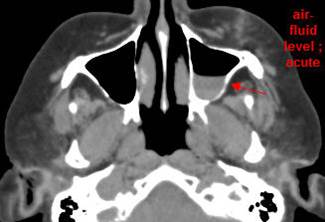

There is evidence of blood products in the paranasal sinuses. [Yes/No]